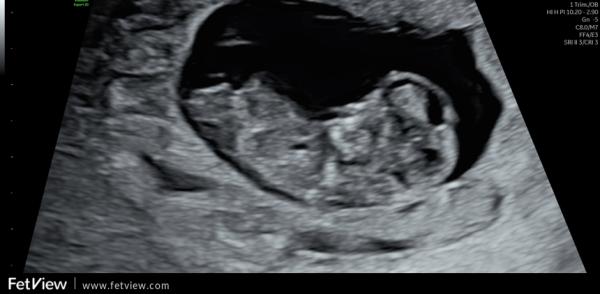

Huhu liebe Letti, ich gucke auch immer mal gerne in die anderen Gruppen rein 🤭 Deine Bilder muss ich wirklich sagen sind sehr schwierig. Würde aber einen Hauch mehr zum Jungen tendieren. Beim Mittleren ist über dem sticht noch ein kleiner kurzer Strich, den haben die Mädels nicht. Ebenso fehlt diese typische Mädchen gabelung vorne. Und bin mir nicht ganz sicher, ob der obere Strich bei (ich glaube bei dem letzten Bild war es) ein ganz kleines mini bisschen mehr nach oben geht. Ich kann es mir aber auch einbilden. Ich muss ehrlich sagen, dass ich die Nub Theorie unfassbar spannend ist und am liebsten den ganzen Tag so Bilder angucken könnte und neugierig bin, was es letztendlich dann ist 🤭

Oh, ich bin ja ganz bei dir. Finde das auch total spannend. Auch wenn das natürlich keine 100% Garantie gibt. Ich muss gestehen, dass ich mich danach ein wenig reingelesen habe und das Ganze trotzdem nicht 100% verstanden habe 🤔😃 Meine Bilder sind aber auch nicht so eindeutig, wie die, die man im Internet (meist) findet. Gerade beim letzten Bild hätte ich eher auf ein Mädchen getippt, weil das für mich so parallel aussah, wo ich eingekreist habe 🥰 Der weiße "Strich/Fleck" oberhalb von dem orangenen Kreis gehört zum Bein. 🤭 Einfach spannend 😍

Ich find es halt interessant, weil die Ärztin bei der Feindiagnostik auch damit anfing und das nochmal erklärt hatte. Schade, dass man den Nub nicht so genau erkennen kann. Oder man kann ihn sehen aber unser ungeschultes Auge bekommt es nicht gebacken 😂 Ich weiß was du meinst. Hab dein Bild frecher weise einfach mal "bemalt" um zu zeigen, was ich meine.

Genau. Das letzte Bild war es. Der untere Strich geht nach unten, der obere nach oben. Es sind nicht beide Parallel verlaufend nach unten.